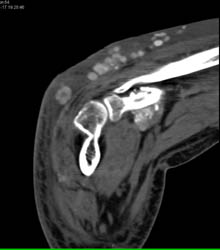

Gout